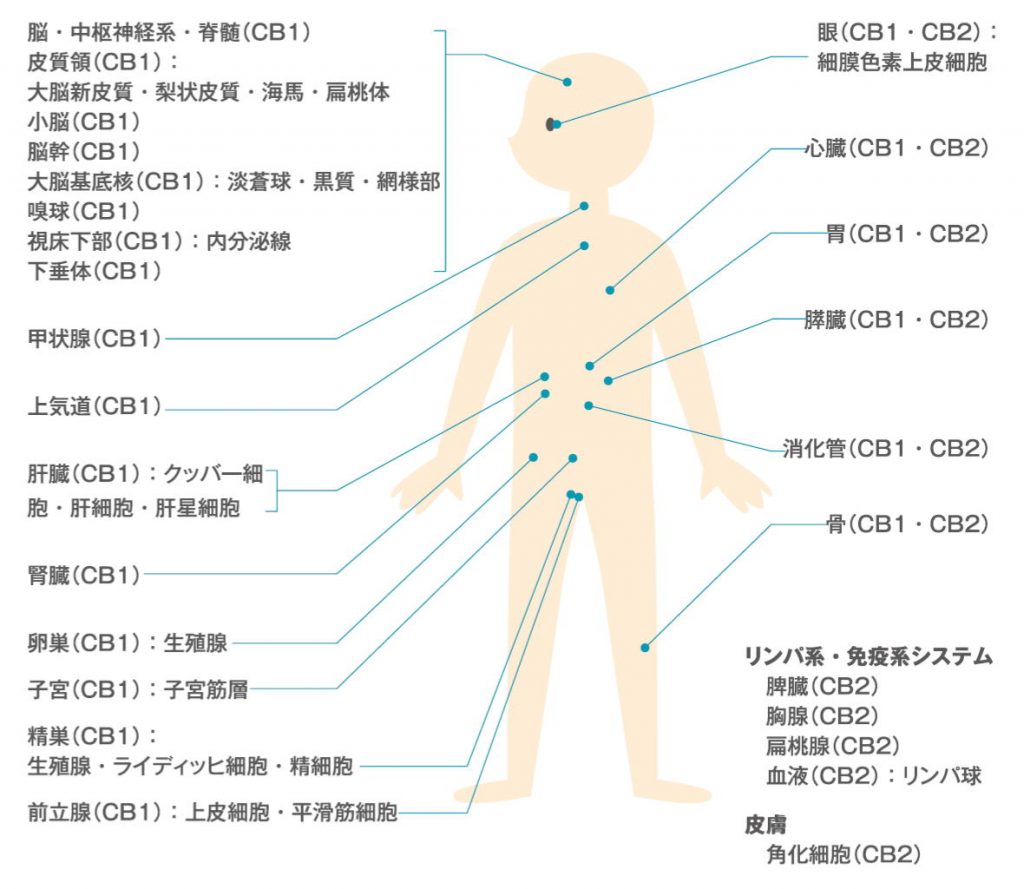

私たちの身体には、本来「エンド・カンナビノイド・システム(ECS)」という

身体調節機能が備わっています。

ECSは「アナンダミド」「2-AG」などの内因性カンナビノイドと「CB1」

「CB2」などのカンナビノイド受容体などで構成されており、食欲、痛み、

炎症、感情、免疫機能など心身のあらゆる機能を調節しています。

CBDはこの「CB1」「CB2」などの受容体に作用しECSの機能を調整するため、

様々な不調を和らげる効果があるといわれています。

CB1受容体が骨形成の減少を調節する

CBDがECSに働きかけることで心身の様々な作用に影響を与えることを

お伝えしましたが、そのECSは骨形成にも影響を与えるといわれています。

2009年に海外で行われた研究では、カンナビノイド受容体の1つである

CB1受容体が、骨組織の吸収と生成を調節することにより骨を保護する

作用があると報告しました。

そのため、CB1受容体に作用するCBDが骨粗しょう症の治療にも効果を示す

可能性があると考えられます。